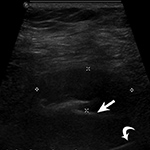

Failed fat-suppression. Coronal T2 fat-saturated image of the ankle with extensive susceptibility artifact due to distal fibular plate and screws shows failed marrow fat suppression involving the distal tibia and hindfoot with demarcation between successful (arrow) and failed suppression in the talus (curved arrow).